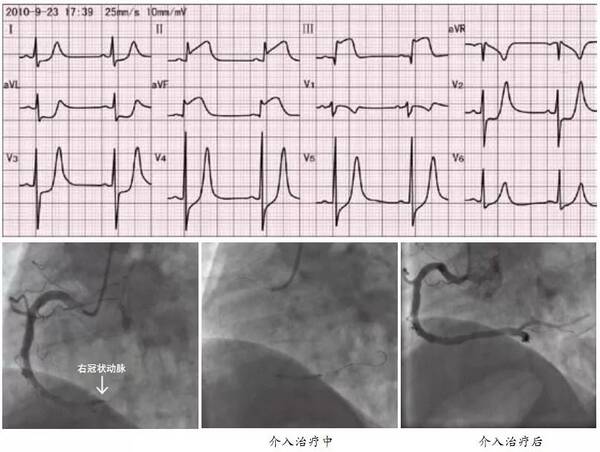

下壁心肌梗死

下壁心肌梗死的罪犯血管定位很难?来试试

心梗造影图片

下壁心肌梗死心电图